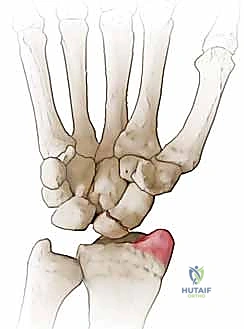

- المرحلة الأولى (Stage I): خشونة وتآكل في المفصل بين القطب البعيد للعظم الزورقي وعظم الكعبرة (الناتئ الإبري الكعبري).

تُعد عملية استئصال القطب البعيد للعظم الزورقي (Excision of the Distal Pole of the Scaphoid) حلاً جراحياً ذكياً ومبتكراً. الفكرة الميكانيكية وراء هذه الجراحة هي: "إذا كان القطب البعيد للعظم الزورقي هو الذي يحتك بعظم الكعبرة ويسبب الألم والخشونة، فلنقم بإزالته مع الحفاظ على باقي هياكل الرسغ".